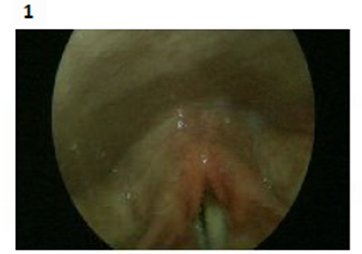

Endoscopic vocal cord examination pictures (one year after the injury) as shown down:

Lt vocal cord weakness with thickening post augmentation. Figures